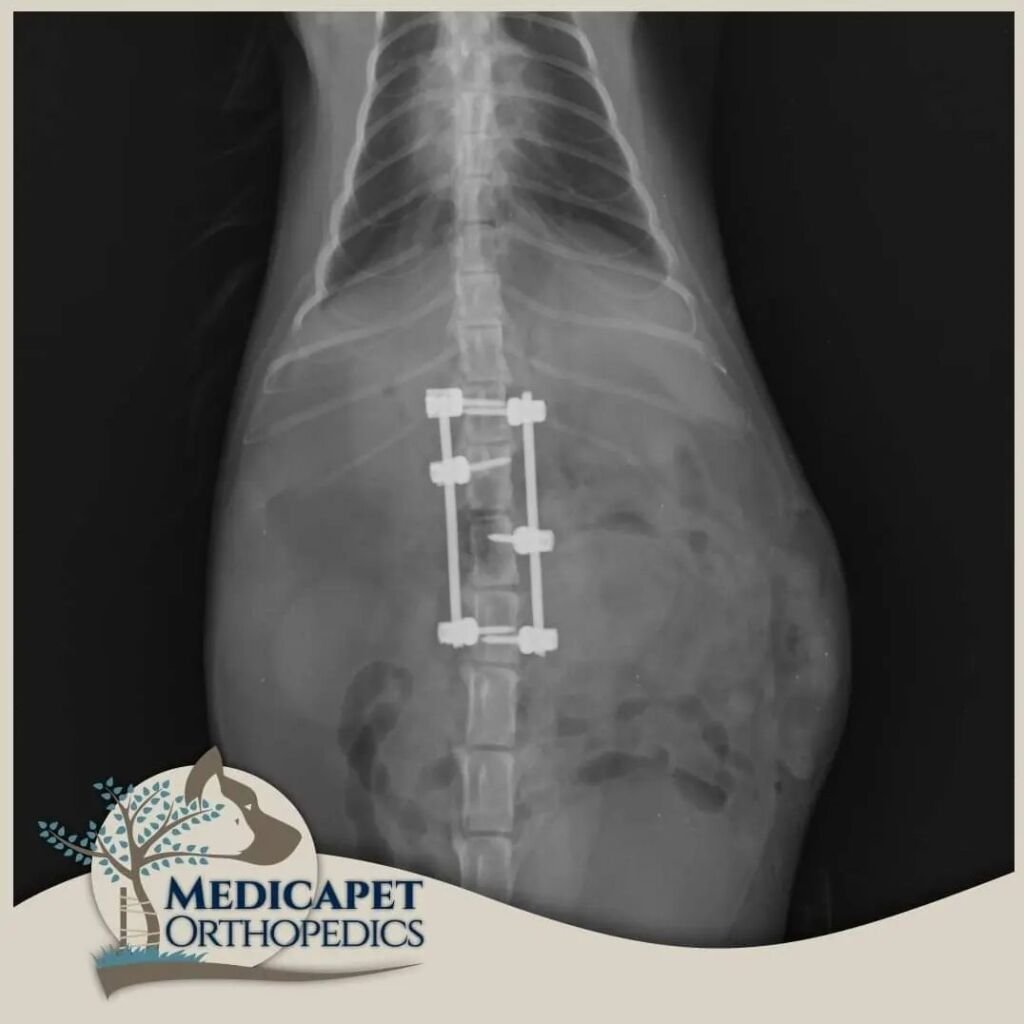

Kemik dokulara paralel seyreden ya da onların içinde bulunan sinir yapıları, kemik hasarlarıyla birlikte zarar görebilir. Yumuşak yapılı sinir dokuları en küçük travmaya karşı hassastır ve korunmaya ihtiyaç duyar. Beyin ve omurilik gibi organlar kafatası ve omurga tarafından korunur, bu nedenle kemik dokuların tedavi ve onarımı sinir dokusuna zarar vermeden yapılmalıdır. Ayrıca bazı sinir hastalıklarında da (örneğin tümörler) kemik dokuya müdahale gerekebilir. Bu yüzden nöroloji ve ortopedi yakından ilişkilidir.

Sinir sistemi; Merkezi Sinir Sistemi (beyin, beyincik, beyin sapı, omurilik) ve Periferik Sinir Sisteminden (gangliyonlar, sinirler, sinir uçları) oluşur. Kliniğe başvuran hastaların çoğunda trafik kazaları, düşme, saldırılar gibi nedenlerle omurga kırıkları, kafatası travmaları veya felç durumları görülmektedir. Bazı ırklarda genetik yatkınlık da omurga sorunlarına yol açabilir.

Nörolojik cerrahide operasyon kadar öncesi ve sonrası bakım da önemlidir. Operasyon sonrası ödem sinir dokularda bası oluşturabileceğinden dikkatli cerrahi, uygun ilaç tedavisi ve gerektiğinde fizik tedavi süreci titizlikle uygulanmalıdır. Sinir dokusu diğer dokulara göre çok daha yavaş iyileşir; küçük bir kesik deride kısa sürede düzelirken omurilikte kalıcı felce yol açabilir.